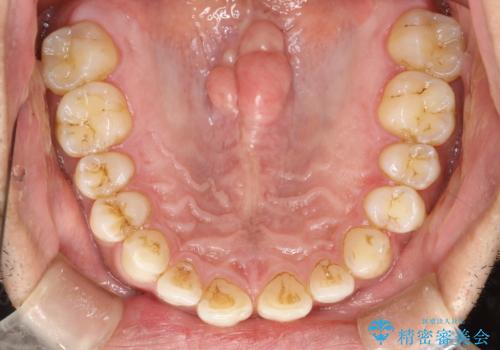

歯と歯の間の着色をPMTCでできる限り除去

- 歯と歯の間の着色を綺麗にしたいとのことで来院されました。PMTC60分で取れる範囲の着色や歯石などの除去を行いました。

毎日丁寧に歯磨きをしていても、日常生活での飲食物などにより着色してしまうことはあります。PMTCでは、歯の表面の凸凹にミネラルを補給して、ツルツルの表面に仕上げます